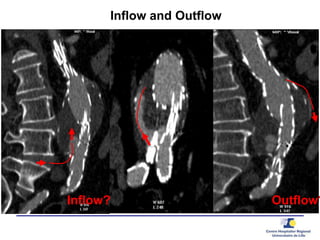

Inflow and Outflow

Inflow? Outflow?

outflow

inflow